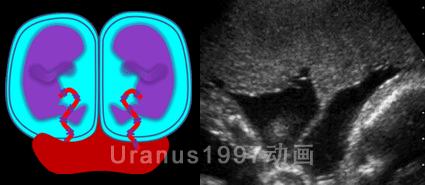

(1)单绒毛膜双胎羊膜分隔与胎盘呈"T"征;

(2)双绒毛膜双胎胎膜融合处夹有胎盘组织,所以胎盘融合处表现为"双胎峰"(或"λ"征);

(3)只有一个胎盘,且有分隔膜,重点观察分隔膜与胎盘连接处形态,胎盘融合处表现为"双胎峰"(或"λ"征)提示MCDA;分隔与胎盘呈"T"征提示MCMA。